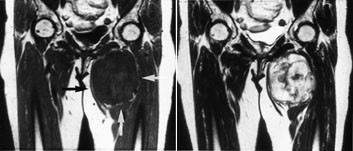

Ved osteogent sarkom og Ewings sarkom kan MR med snittplan i knokkelens lengdeakse nøyaktig fastslå øvre og nedre grense for tumorutbredelse i beinmargen (fig 5), påvise metastaser innenfor samme margrom og innvekst i ledd. Dette er forhold som har stor betydning for omfanget av kirurgiske inngrep. Som regel har tumor på diagnosetidspunktet brutt gjennom knokkelen og gitt opphav til en ekstraossøs komponent. Med snittplan perpendikulært på knokkelen kan MR vise om tumor affiserer kar og nerver, og hvilke muskler den ligger an mot eller infiltrerer. MR kan styre biopsitakingen til de områder av tumor hvor det er størst sannsynlighet for å finne representativt vev.

Konvensjonelle røntgenbilder er første trinn i utredningen av mistenkte bløtvevssvulster (12). De viser underliggende skjelettdeformitet, beinaffeksjon og bløtvevsforkalkninger. Forkalkninger kan ikke påvises med MR. MR er allikevel den beste metoden, fordi den i tillegg til å vise de anatomiske forhold også fremstiller væske, nekrose, blødning, fett og annet bløtvev (fig 6 – 8). Basert på vekstmønster og signalforhold kan vevsspesifikk diagnose stilles i 20 – 40 % av tilfellene. Det er oftest ikke mulig å angi om en bløtvevstumor er benign eller malign. Nekrose er den enkeltfaktor som sterkest peker i retning av malignitet. Andre faresignaler er stor tumor, uskarp avgrensning med omgivende ødem, heterogent signal og beinaffeksjon. Men høymaligne bløtvevssvulster kan være velavgrenset med en pseudokapsel.